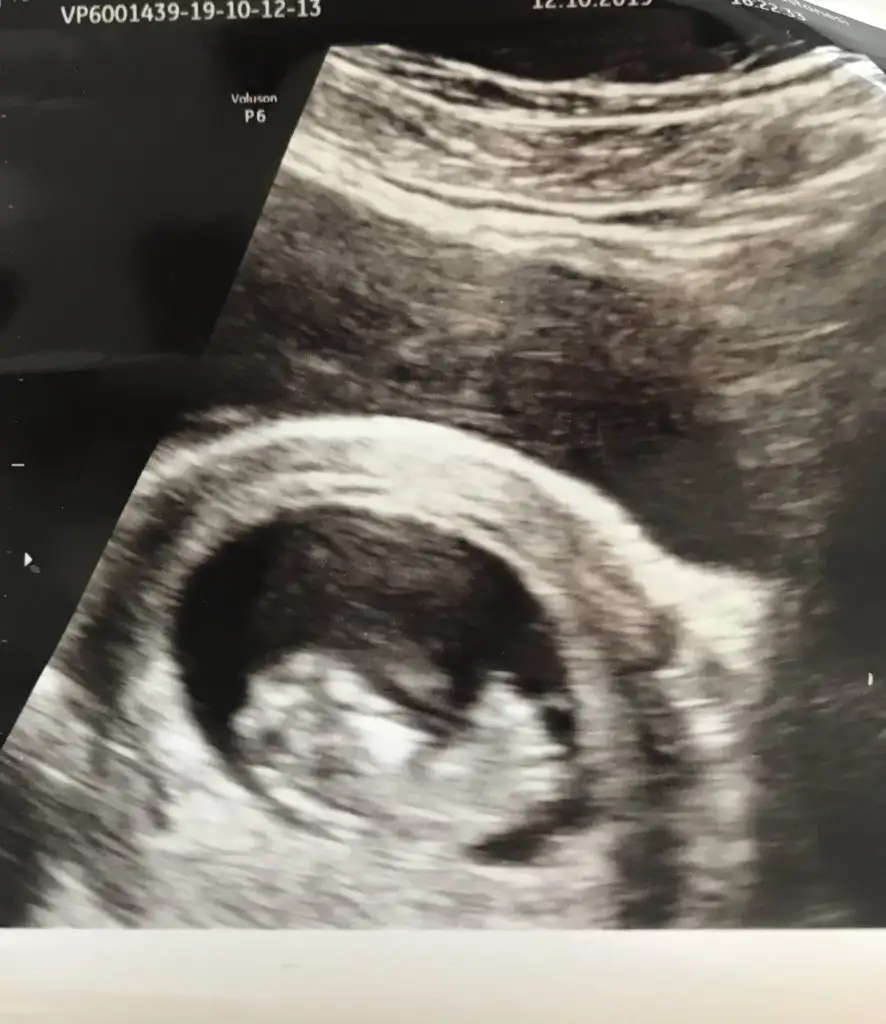

Kizz14 haftalık doktor yüksek ihtimal kız ama yüzde 100 de diyemem dedi sizce nedir acaba

KizzKızlar tahmini olan var mıı

İnsallah teşekkürler

Bebeğim erkekmişAyy kız bu Bebiş bence

Bana bak nasıl da net söylemişim hayırlısı canım benim de iki oğlum var en iyi arkadaşlar sağlıkla gelsin inşallahBebeğim erkekmişİkinci oğlan geliyor.Yorum için teşekkür ederim